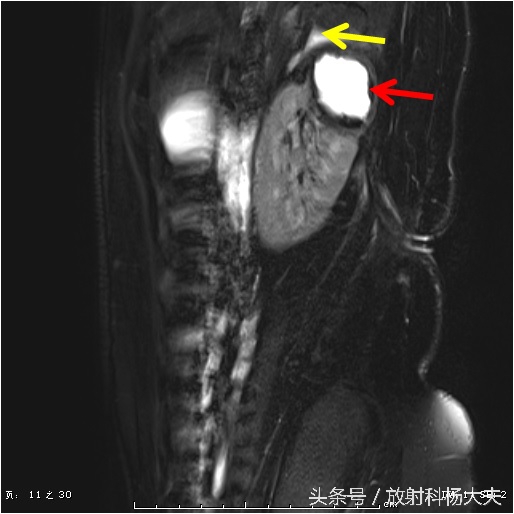

这个囊性病变到底是什么?囊性肿瘤?有无办法继续明确呢?有!那就是MRI,除了进一步明确,还能更清楚的显示窦道的走行。下图这个序列,叫DWI,红箭所示的白白的东西,证明这是一个脓肿!

终于搞清楚了,原来一个月前的腰痛,是肾脏的脓肿,而且MRI上还能清晰的显示脓肿破口的位置,下图中黄箭所示(红箭为脓肿)。

还有那弯曲的窦道。